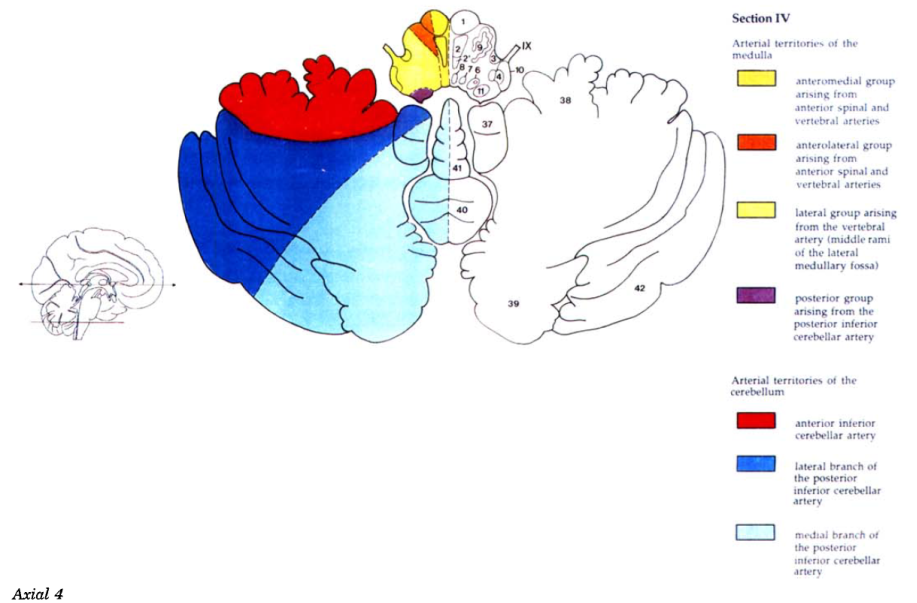

Cerebral vascular territories

Brainstem